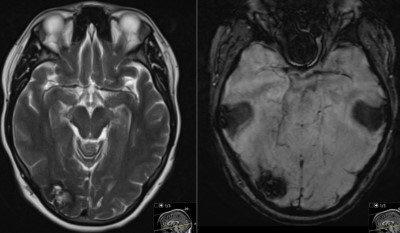

- Pre-Op